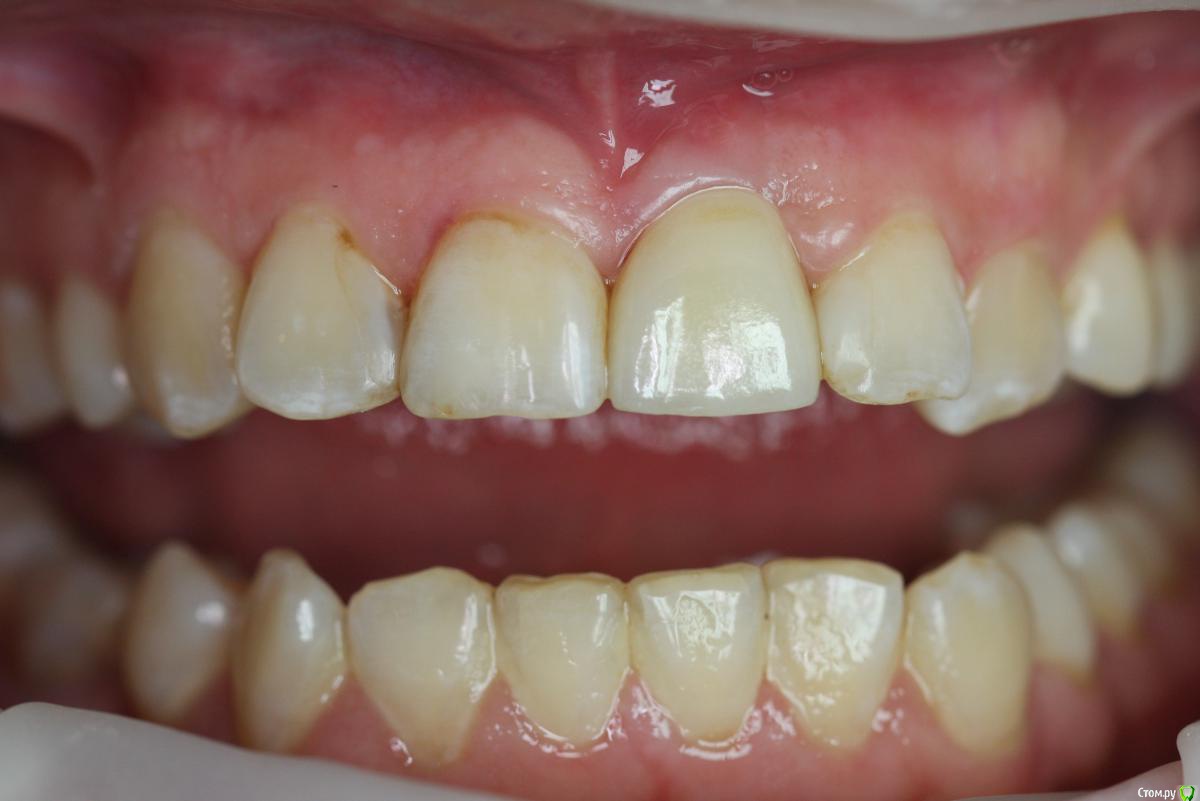

Zorrro Опубликовано 29 февраля, 2016 Автор Поделиться Опубликовано 29 февраля, 2016 (изменено) Через два дня пациент меня неприятно удивил.И ,безусловно,правильно было бы отменить операцию и ограничиться удалением,но… Вот такой был сюрприз под носом с нечищенными зубами.Обговорив риски,перекрестившись начали.Во время операции фото не делал.Слизистая в проекции 21 была сильно истончена острым гнойным процессом,буквально светилась.в итоге после эвакуации гноя промыл фурацилином,установил анкилос А11,подсыпал остеопласт вестибулярно и укрыл это всё сст из бугра в качестве мембраны.ещё один сст пошёл навременный абатмент в виде "шашлыка".Через 10 дней Через 4 месяцас рекомендацией замены пломбы на 12 у своего доктора мы ипопрощались.пациентка осталась глубоко удовлетворённой,а это главное. Изменено 29 февраля, 2016 пользователем Zorrro 4 Ссылка на комментарий